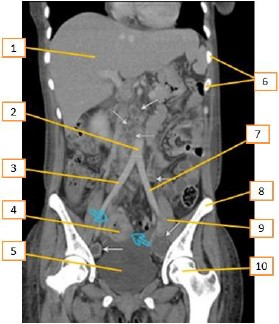

Tomografia computadorizada é um procedimento não invasivo de diagnóstico por imagem que combina o uso de raio-x com computadores especialmente adaptados. É utilizado para criar imagens detalhadas dos mais variados tecidos do corpo humano. O procedimento é realizado através da emissão de raios X rotacionada ao redor do corpo, que, por sua vez e de forma variada, a depender de cada tecido, atenua o feixe de raios-X, que são absorvidos por detectores de radiação, que enviam então os dados para um sistema computacional. Esse sistemconsegue transformar a radiação, através de seus detectores, em um sinal digital no qual se tem a imagem formada muitas vezes mais fidedigna que as imagens radiográficas. Entre os vários assuntos que devem ser conhecidos, a anatomia é fundamental.

Disponível em: https://protocolos-de-tc.webnode.page/abdome/. Acesso em 12/11//2023(Adaptado)

Com base no texto acima e de acordo com a região anatômica apresentada, os números que aparecem na imagem estão corretamente descritos em